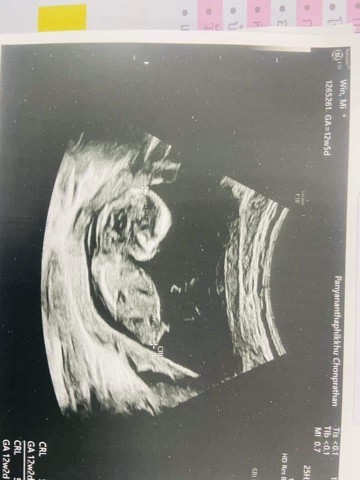

ตอน 12 week 5 วัน แต่ยังไม่รู้เพศ #ทีม21มีนาคมจ้า